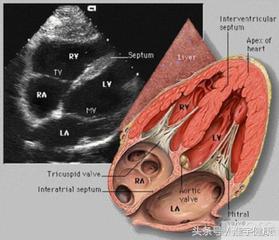

三、心脏彩超

心脏彩超是唯一能动态显示心腔内结构、心脏的搏动和血液流动的仪器,对人体没有任何损伤。心脏探头就像摄像机的镜头,随着探头的转动,心脏的各个结构清晰地显示在屏幕上。

主要检查心脏的形态学有没有什么异常,以及心功能是否正常,特别对先天性心脏病是首选的检查方法

心脏彩超显示的是心脏的内部结构异常,房室大小的变化以及血流的速度和方向,在心脏病的诊断中具有重要的价值.一般心情,睡眠对检查的结果有一定的影响,建议您避免紧张情绪,按时休息即可。